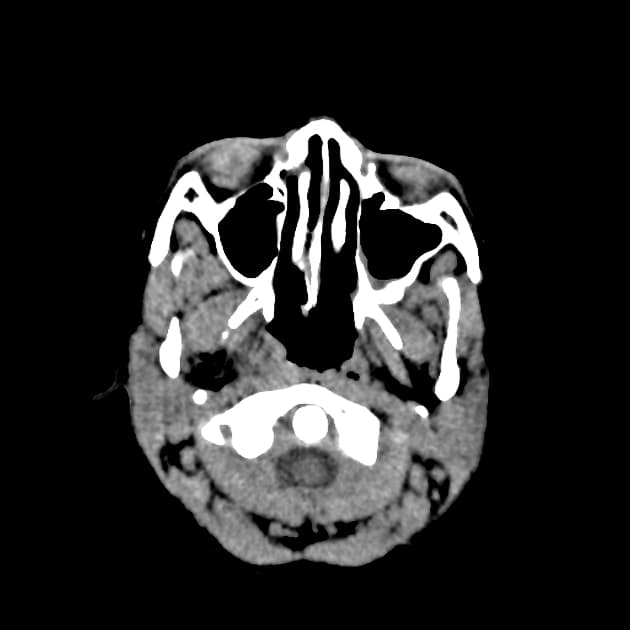

Temporal bone rhabdomyosarcoma with leptomeningeal metastases

Có một khối u dạng thùy, tăng quang không đồng nhất, khu trú tại ống tai ngoài, hòm nhĩ, các tế bào chũm và tai trong bên trái. Khối u có tín hiệu thấp trên các hình ảnh T1 và tín hiệu cao trên các chuỗi T2 và FLAIR. Đã ghi nhận sự xâm lấn vào góc cầu tiểu não bên trái. Có hiệu ứng khối đi kèm gây chèn ép lên não giữa, cầu não và não thất tư.

Phía trước, khối u tiếp giáp với thùy thái dương dưới. Sự xâm lấn vào phía trong dẫn đến tiếp giáp với khoang động mạch cảnh bên trái, với các khoảng trống tín hiệu dòng chảy vẫn được bảo tồn trong các mạch máu lân cận. Xâm lấn ra phía trước ngoài liên quan đến tuyến mang tai kèm theo một hạch bạch huyết tuyến mang tai lớn. Có tăng quang màng não dạng nốt dày dọc theo lều tiểu não bên trái, thân não, màng não vùng nền, vòm sọ và bán cầu tiểu não, phù hợp với lan tỏa màng não mềm.

THẢO LUẬN: Kết quả giải phẫu bệnh xác nhận sarcoma cơ vân. Hình ảnh cho thấy một khối u ác tính tiến triển mạnh khu trú tại nền sọ với sự lan rộng tại chỗ và xâm lấn nội sọ. Sarcoma cơ vân là loại sarcoma mô mềm phổ biến nhất ở trẻ em và thanh thiếu niên, thường liên quan đến vùng đầu cổ, bao gồm các vị trí cạnh màng não như tai giữa, xương chũm và khoang quanh hầu.